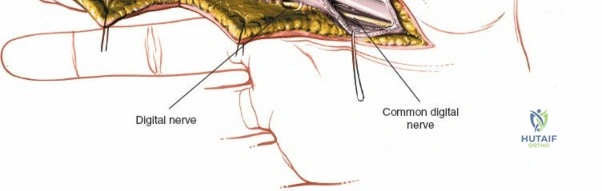

The digital neurovascular bundles (NVBs) run along the radial and ulnar sides of each digit, volar to the collateral ligaments, providing sensation and vascularity. Proper identification and protection of these bundles are paramount during any volar dissection. Proximally, the median nerve gives rise to recurrent motor branches to the thenar muscles and sensory branches to the thumb, index, middle, and radial half of the ring finger. The ulnar nerve supplies the hypothenar muscles, adductor pollicis, and interossei, along with sensory innervation to the little finger and ulnar half of the ring finger. The palmar arches (superficial and deep) provide critical vascular supply to the hand.

- Palmar Incision: Can be made as a curvilinear extension from the digital Bruner incision, often curving towards the thenar or hypothenar eminence, or as a transverse incision in line with the distal palmar crease. Incorporating a laceration directly into the incision is always preferred to minimize additional skin damage.

After marking the incision, the skin and subcutaneous tissues are carefully incised. In the digits, the triangular skin flaps created by the Bruner incision are elevated using fine skin hooks or small self-retaining retractors. Dissection should proceed in the subcutaneous plane, superficial to the digital neurovascular bundles, which run along the radial and ulnar borders of the digit, immediately adjacent to the flexor sheath.

Care must be taken to identify and protect these bundles. Any existing lacerations or hematomas are debrided. The digital nerves and vessels are carefully dissected free from the surrounding connective tissue and retracted, typically dorsally and laterally, using vessel loops or fine retractors to provide clear access to the underlying flexor sheath.

Neurovascular Bundle Management

If digital nerves or vessels are lacerated, they are repaired after tendon repair or at a separate stage depending on the complexity.

- Nerve Repair: Digital nerves are repaired primarily using microsurgical techniques (e.g., epineurial repair) with fine monofilament sutures (e.g., 8-0 to 10-0 nylon) under magnification. Tension-free repair is paramount.